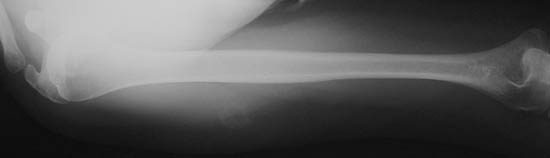

| The plain film radiographic appearance of myositis ossificans can be more subtle, with a rounded focus of soft tissue calcification as in this case involving the upper outer arm. These lesions can mimic a malignant bone tumor, but they are a reactive process--a form of osseous metaplasia in response to trauma. |